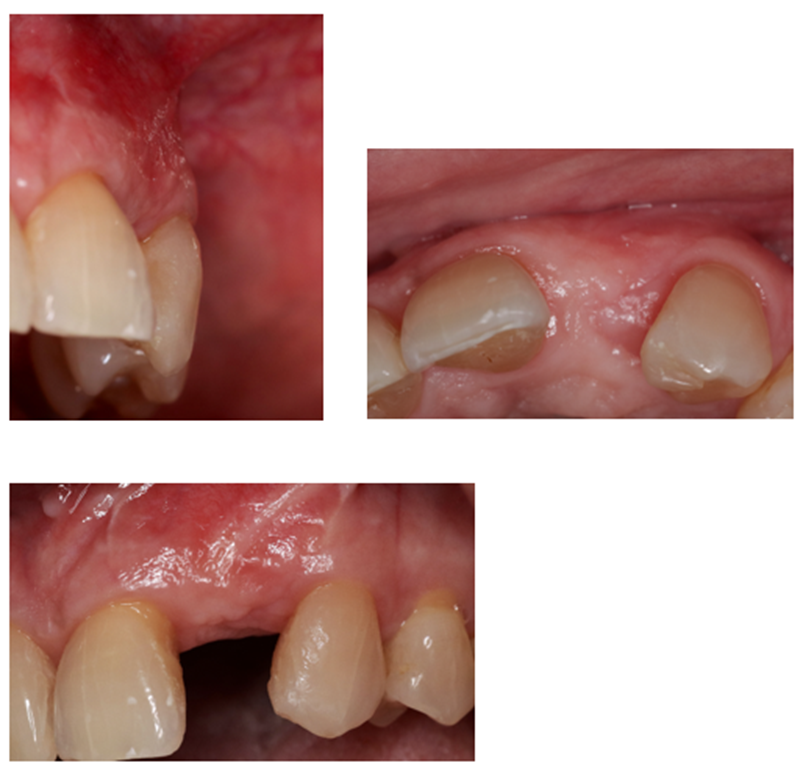

Após 8 meses da ROG, foi instalado um implante Cone Morse Due Cone 3,5 x 11mm através da técnica de cirurgia guiada por computador (Vídeo 2).

A escolha da técnica empregada justifica-se pela menor morbidade do procedimento cirúrgico e melhor acurácia no posicionamento do implante; conforme demonstrado por Nomiyama et al., 2022, ao utilizar o Sistema Implacil de instalação de implantes pela técnica guiada por computador. Imediatamente após a colocação do implante, foi instalada prótese provisória sem contato oclusal sobre pilar Ideale 3.3 x 4. Depois de quatro meses de pós-operatório, foi feito o escaneamento do componente protético utilizando transferente digital Exocad e a prótese em zircônia foi finalizada (Figuras 4 e 5).

Portanto, ao se comparar o resultado obtido ao final do tratamento da paciente com a condição inicial (Figura 6), podemos sugerir que este tipo de abordagem terapêutica é capaz de devolver estética e função mastigatória para este perfil de condição clínica tão desafiadora.